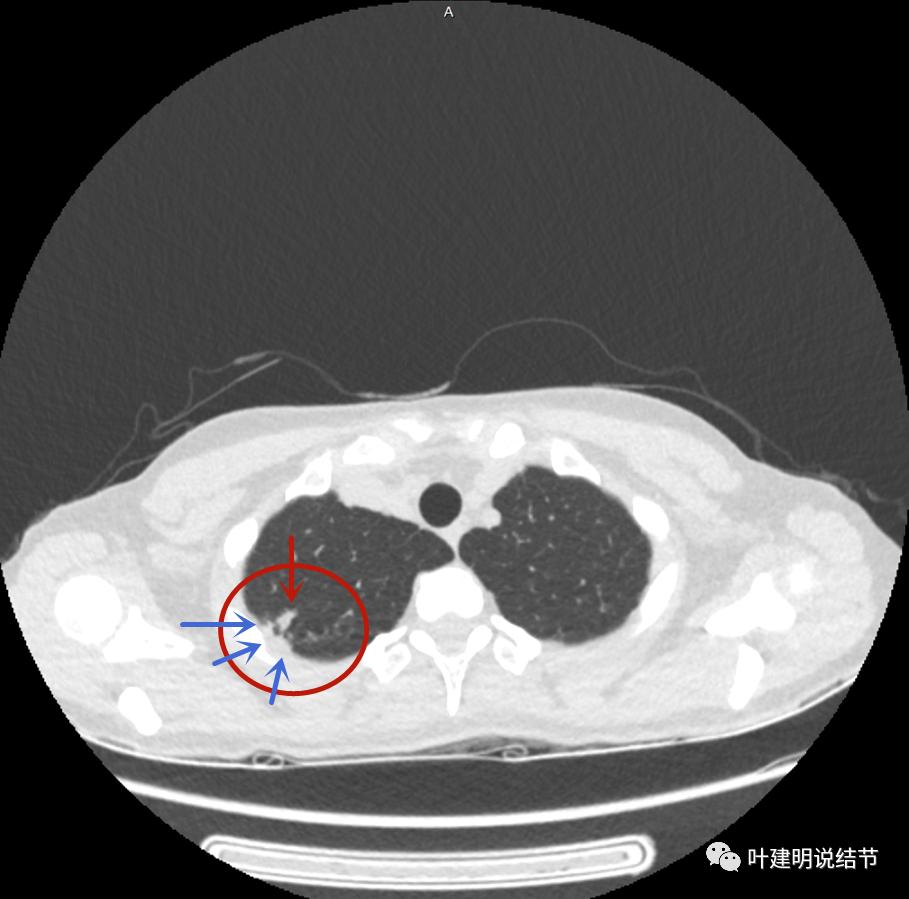

病灶邻近胸膜异常增厚(蓝色箭头)

有卫星灶(绿色箭头),邻近胸膜明显增厚,且模糊,边不清

邻近胸膜增厚

主病灶此层面似三角形,邻近胸膜增厚(蓝色箭头),结节实性部分密度较高(粉色箭头),边缘显模糊(砖色箭头)